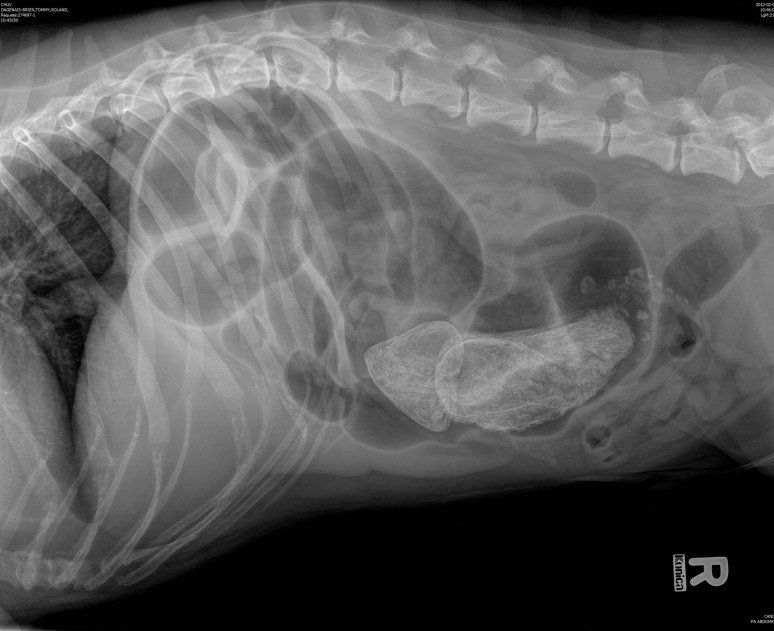

Signalement: Labrador de 5 ans, mâle castré.

Histoire clinique: Amaigrissement progressif depuis 3 mois, avec courts épisodes de selles liquide, mais sans vomissement. Hypoprotéinémie.